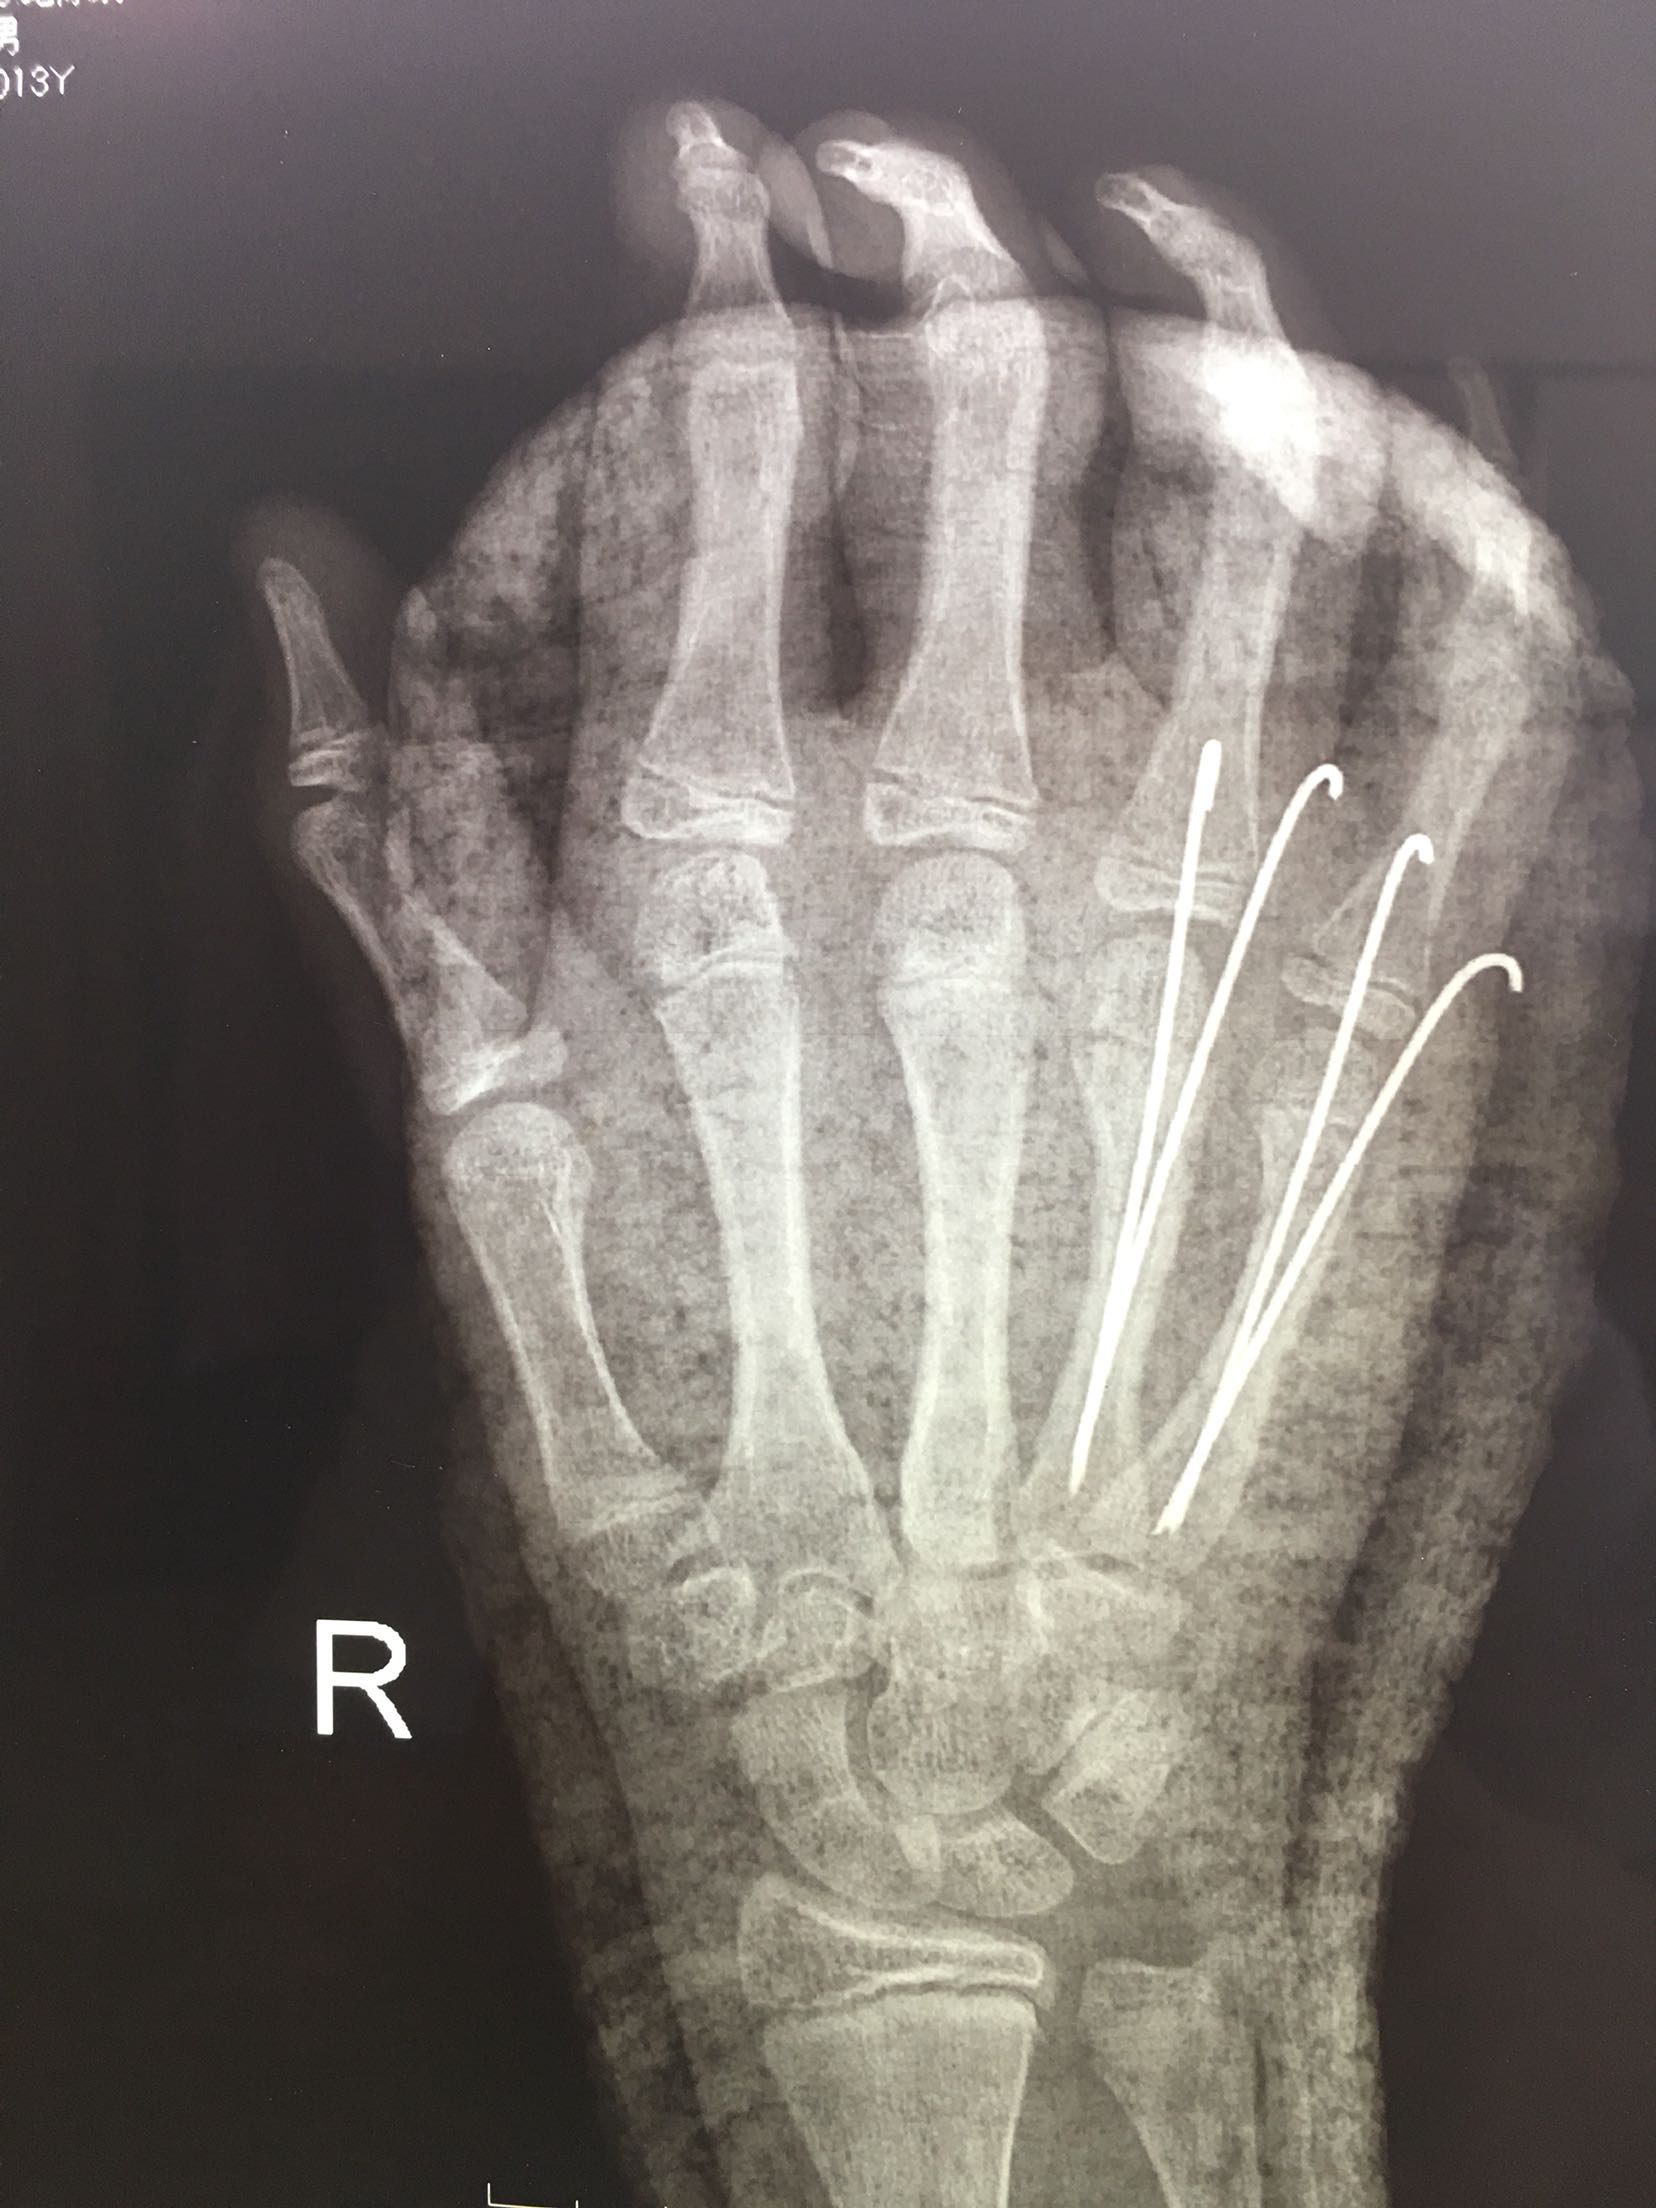

右第四,五掌骨骨折(微创)

患者,男,13岁,撞伤后右手肿痛,活动受限1天入院。

右手肿胀明显,局部皮色青紫,皮温稍高,第四,五掌骨头处压痛,纵叩痛阳性,掌指关节活动受限,末梢血运感觉正常。

完善检查,在臂丛麻醉下行闭合复位内固定术,术后抗炎,消肿止痛等对症处理,右手石膏托制动。